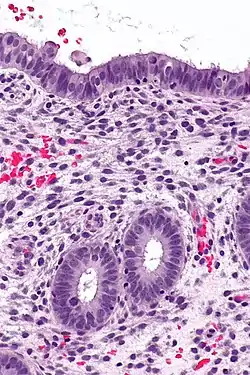

Endometrioid adenocarcinoma from biopsy. H&E stain.

Micrograph of decidualized endometrium due to exogenous progesterone. H&E stain.

Micrograph showing endometrial stromal condensation, a finding seen in menses.